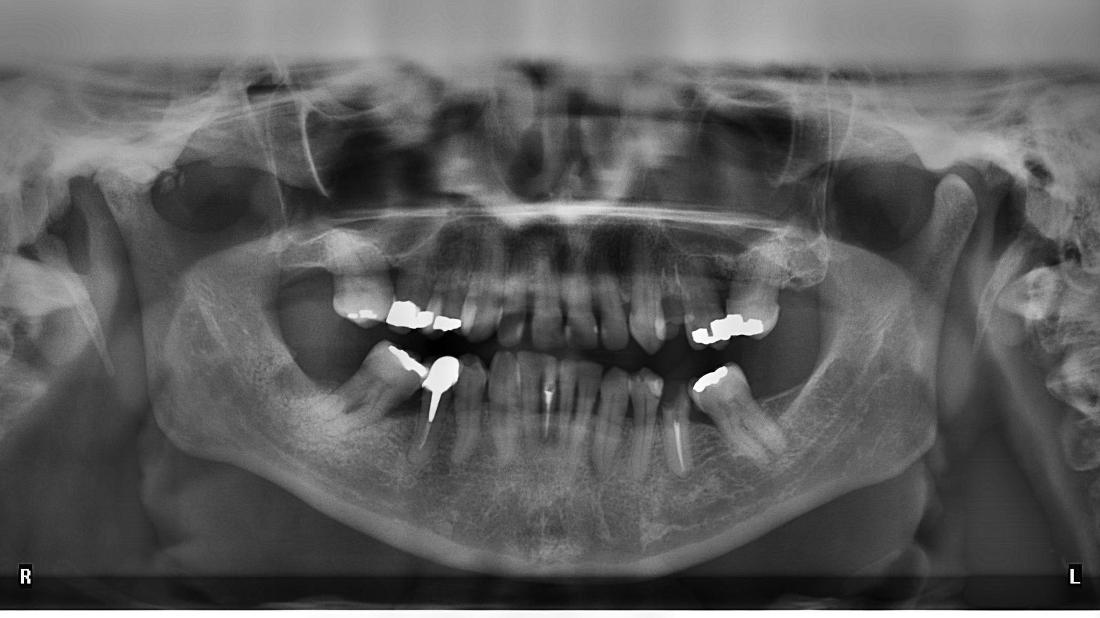

Panoramic XRay Of Crowding Teeth Stock Photo 204889417 Shutterstock Crowded Teeth X Ray The primary causes of teeth crowding include teeth larger than the jaw or a jaw that is too small. in dental crowding therapy, it is important to quantify the lack of space in the dental arch in order to choose an appropriate orthodontic. Losing baby teeth too early can. dental crowding, also referred as swarming, can be characterised. Crowded Teeth X Ray.